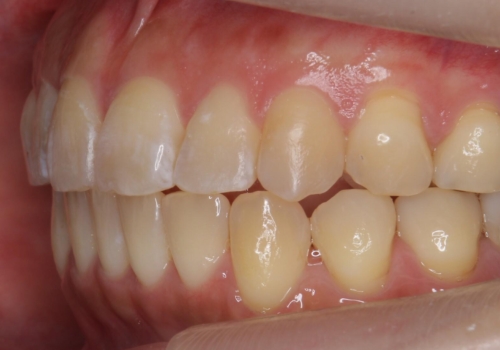

前歯を引っ込めたい 歯を抜かずにマウスピースで

- 前歯の突出を主訴に来院。

上の奥歯を後ろに下げて治療をしました。